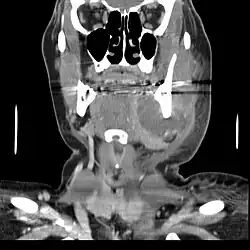

.jpg)